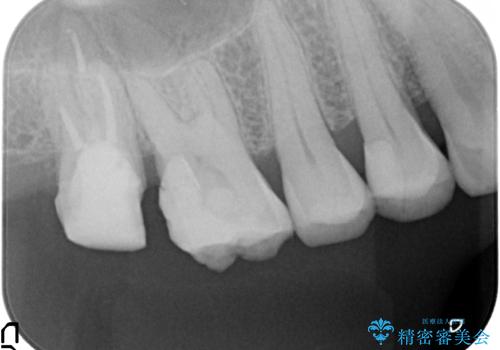

歯髄方向 歯肉方向へと深い 2種類の大きな虫歯

#17は失活歯で歯肉方向への縁下カリエス、#16は生活歯であるものの歯髄ギリギリの処置となるであろうとが予想される治療です。

深い虫歯には歯周外科、マイクロスコープを用いた丁寧な虫歯の除去を行うことで歯の神経や歯そのものを残すことが可能になります。